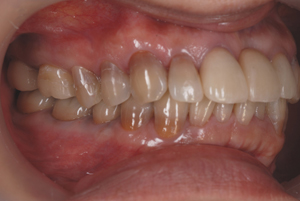

■口の中の金属を白くする症例

初診時

セット後